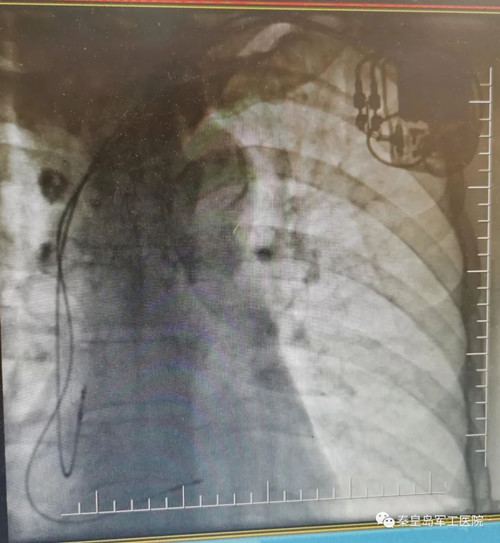

(心内科主任王春梅正在为患者进行起搏器植入)